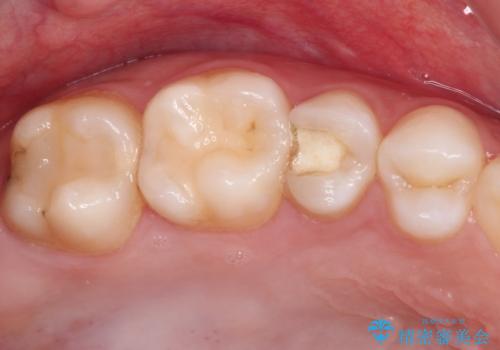

かなり深い位置にまで虫歯が及んでいたため、かなりの量を引っ張り出す必要があり、残された歯根は短く小さい状態となりました。

今後も定期的にレントゲンを撮るなど、経過を追っていく必要があります。